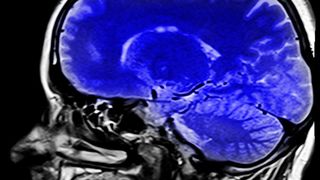

Kernspintomograf im Chipformat entwickelt Hirnimplantat: Das MRT in unserem Kopf?

Das MRT, auch Kernspintomografie genannt, ist ein wichtiges bildgebendes Verfahren insbesondere der medizinischen Diagnostik. Nun haben Tübinger Max-Planck-Forscher die Technik auf ein (implantierbares) Chipformat geschrumpft. Mit solch einem Hirnimplantat hoffen die Forscher Hirnfunktionen und deren Störungen sehr viel detaillierter untersuchen zu können.

Tübingen – Neurowissenschaftler und Elektroingenieure des Max-Planck-Instituts für biologische Kybernetik in Tübingen und der Universität Stuttgart haben ein Implantat entwickelt, das Forschern erstmals hochauflösende Daten zur neuronalen Aktivität im Gehirn liefert.

Die Erfindung ermöglicht die Kombination räumlicher Informationen zur Hirnphysiologie mit Erkenntnissen zu Wechselwirkungen von Nervenzellen in Echtzeit. Das Implantat vereint die Funktionalität eines Magnetresonanztomografen (MRT) auf einem winzigen Chip.

Die haarfeine Sonde besteht aus einem winzigen Magnetresonanztomografen und kombiniert die Vielseitigkeit bekannter räumlicher MRT-Analysen mit der Genauigkeit eines implantierbaren Sensors, der an einem Punkt im Gehirn neuronale Ereignisse in Echtzeit messen kann.